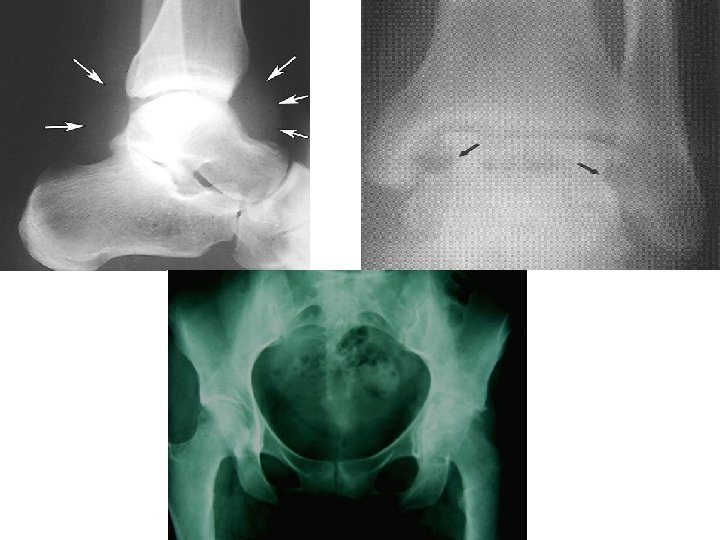

SEPTIC ARTHRITIS • Radiographic changes – Early: • Soft tissue swelling Joint space widening – Late (2 -3 w): • Erosion • Joint space narrowing

UNSTABLE PELVIC FRACTURE • Pelvis – 2 innominate bones + 1 sacrum – Bond together by strong ligamentous complex maintain stability, vertically & horizontally – Major vessels close to the bone

UNSTABLE PELVIC FRACTURE • Pelvic fracture (pelvic ring fracture) – Stable • Configuration • Hemodynamic – Unstable • Configuration • Hemodynamic • Mechanism of injury : – High energy trauma – Force direction (4) : • • Lateral compression Anterior Posterior compression Vertical shear Combined

• Clinical evaluation : – Perform primary survey – Initiate resuscitation. Adress life threatening injuries – In suspicion of pelvic fracture, check : Leg length discrepancy Pelvic instability test can only be performed once Hematoma in flank, around iliac crest, perineum Urethral injury often accompanies pelvic fracture blood in MUE, butterfly hematoma, floating prostate • Vaginal or rectal perforation by fracture fragments • Pelvic AP X-ray using portable X-ray • FAST Focused Assesment Sonography for Trauma • •